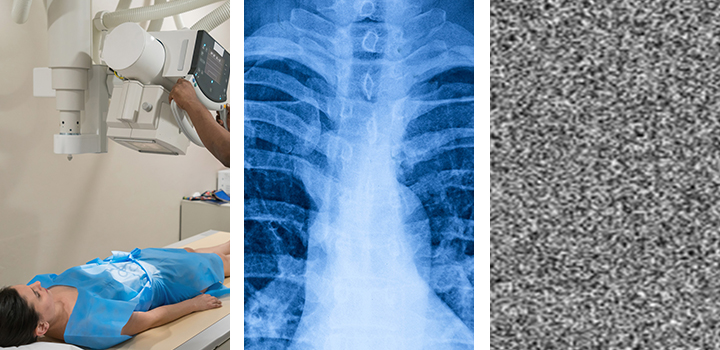

Computer scientists have developed a breakthrough way to encrypt medical images such as X‑rays, CT scans and MRIs, keeping them secure even if hospital networks are breached.

Medical imaging systems have been repeatedly identified as weak points, with many relying on legacy protocols that were never designed to be exposed to the internet, making image‑level encryption an urgent priority.

Image‑level encryption changes the situation entirely. Even if attackers breach a server, intercept a transfer, or access a PACS archive, the images remain unreadable without the key.

In addition to this speed, the new method integrates with existing systems, works across image types such as x-rays and MRIs, is lightweight enough for hospital servers, and can handle high-volume environments, such as emergency radiology.